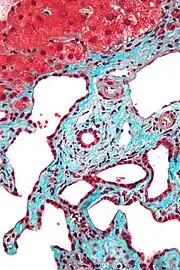

Micrograph of a bile duct hamartoma. Trichrome stain. Intermediate magnification

Micrograph of a bile duct hamartoma. Trichrome stain, high magnification